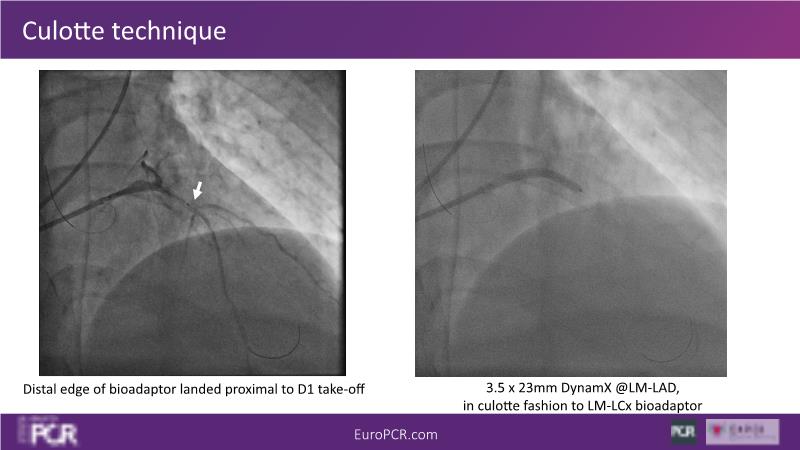

Join this session to delve into the unmet needs concerning drug-eluting stents (DES), including poor long-term clinical outcomes, with up to a 50% MACE rate at 10 years, and a non-plateauing 2-3% annual event rate. Explore how DynamX Bioadaptor technology addresses these challenges by maintaining the established flow lumen and restoring hemodynamic modulation of the artery. Discover the sustained clinical benefits demonstrated in a 2-year RCT, potentially establishing a new treatment standard for CAD patients. Gain insights into patient types benefiting most in clinical practice, such as those at higher risk of restenosis (e.g., LAD disease, long lesions, small vessels, co-morbidities), and younger patients with longer lifespans.